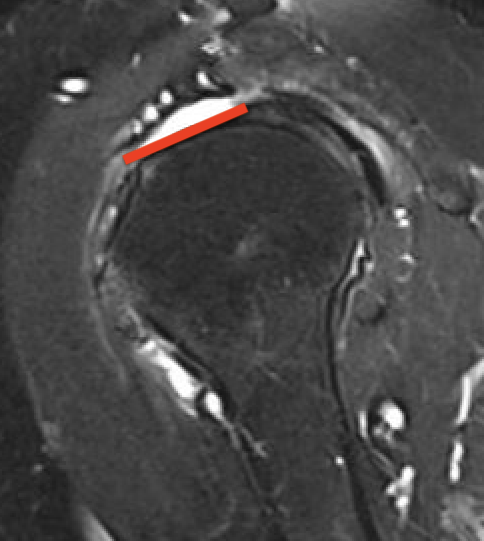

Small full thickness rotator cuff tear of supraspinatus - retracted to footprint

Large full thickness tear of supraspinatus and infraspinatus tendon - retracted to midhumeral head

Massive rotator cuff tear of the supraspinatus and infraspinatus tendon - retracted to glenoid